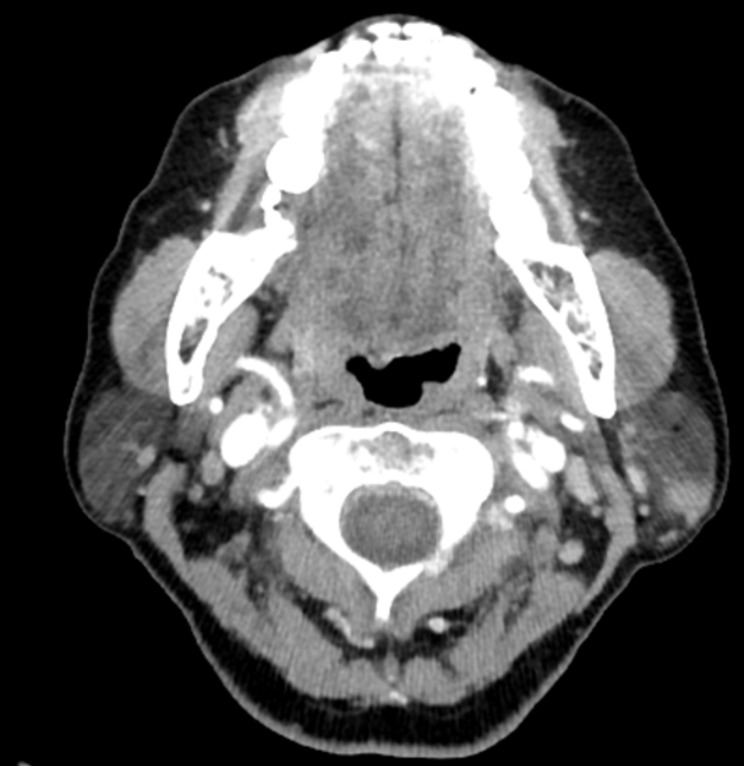

Backgrounds: Preoperative imaging, particularly with magnetic resonance imaging (MRI) and computed tomography (CT) scans, plays a crucial role in distinguishing between benign and malignant parotid gland tumors, while the reliability of Ultrasound-Guided Fine Needle Aspiration (FNA) in diagnosing these masses remains a topic of debate.

Methods: This two-center retrospective analysis was conducted on 347 patients with parotid gland tumors who had FNA and preoperative imaging (CT or MRI). All patients underwent surgery and final histopathological examination was available, along with complete medical records between January 2008 and May 2023.

Results: Among the 347 patients, 318 (92%) had benign and 10 (3%) had malignant tumors based on FNA, with 19 (5%) unsatisfactory specimens. Final histological diagnosis revealed 303 (87%) benign and 44 (13%) malignant lesions, with a false-negative rate of 10.6% for FNA. Multivariate analysis identified irregular shape and invasion as independent predictors of malignancy in patient with benign or unsatisfactory FNA results. The odds ratio for irregular shape was 3.06 and for invasion was 12.73.

Conclusion: Imaging characteristics, such as irregular shape and invasion may indicate towards malignant parotid tumors, even in patients with false-negative benign findings in FNA.